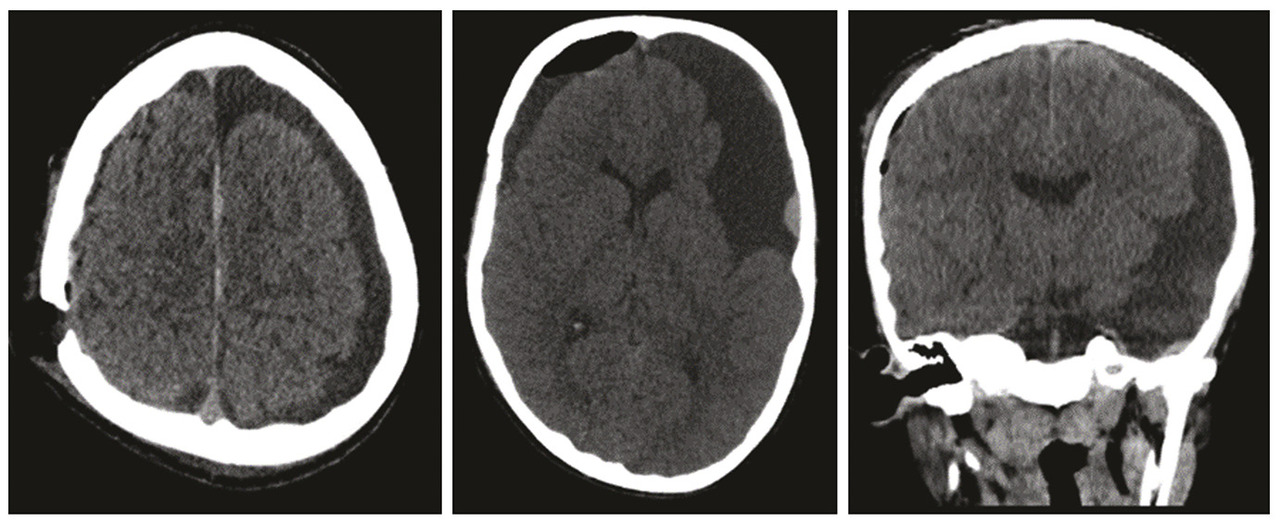

Un enfant de 12 ans est victime d’un traumatisme crânien minime occasionnant une diplopie. Le scanner cérébral montre deux hématomes sous-duraux hémisphériques chroniques ayant ressaigné et une volumineuse lésion kystique temporale gauche. Le patient a été opéré, avec évacuation de l’hématome sous-dural droit (fig. 1). Une imagerie par résonance magnétique (IRM) cérébrale a été réalisée pour mieux caractériser la formation kystique et pour le bilan étiologique du saignement ; elle montre une formation kystique extra-axiale temporale gauche renfermant un sédiment hémorragique en rapport avec un kyste arachnoïdien remanié, et un hématome sous-dural hémisphérique gauche d’allure plutôt chronique (fig. 2). Aucune autre malformation ne pouvait expliquer le saignement. Le diagnostic retenu est celui d’un kyste arachnoïdien remanié compliqué d’hématomes sous-duraux.